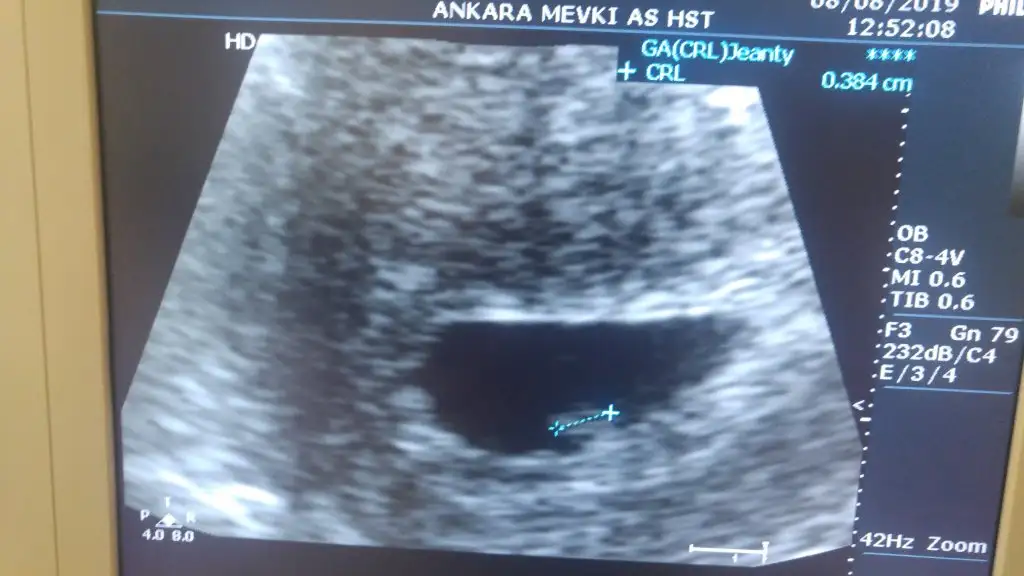

Biz cok şükür gördük bebegi karindan bakti once cok minik bir bebek var ama secilmiyo istersen alttan bakalim dedi. Kabul ettim hemen tabiki 🙊 Alttan bakınca daha net gördü bebegi. Banada gosterdi bak mercimek kadar dedi 😱 kalbi de atiyor bir sorun yok dedi. Hatta Sesi acti ama ben duyamadim.

Haftaya net duyarsin annesi daha cok minik dedi . 0.384 cm 😊 sata gore 7+ 3 ama 6 haftanin icindesin dedi. Buraya kadar hersey süper. Fakat Simdide troid cikti. Tsh degerim 9. Cikti dahiliye sevk etti. Troid ilacina basladik. 😶 Bunada binlerce şükürler olsun. Rabbim dermansiz dert vermesin insallah. 😊Ve dilerim tez zamanda sen ve görmeyi bekleyen diger annelerde görür bebislerini. 💕

• 20190808_113115.webp

20190808_113115.webp

29,2 KB · Görüntüleme: 62